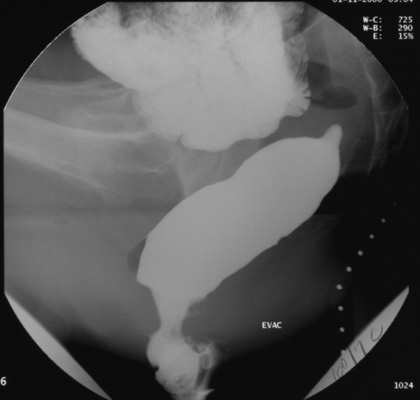

intermittently

during defecation

Videofluorography is also done while

the patient performs the following maneuvers: resting state, squeezing and finally, rectal evacuation. In the latter phase of the

study, key events can also be recorded with intermittent digital imaging.